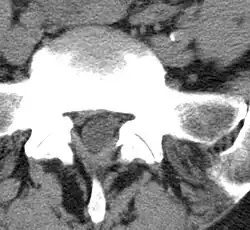

Mithilfe von Bildgebenden Verfahren, wie Computertomographie oder Magnetresonanztomographie, können degenerative Veränderungen der kleinen Wirbelbogengelenke in Relation zum Spinalkanal bzw. zu den Spinalnerven gut beurteilt werden.